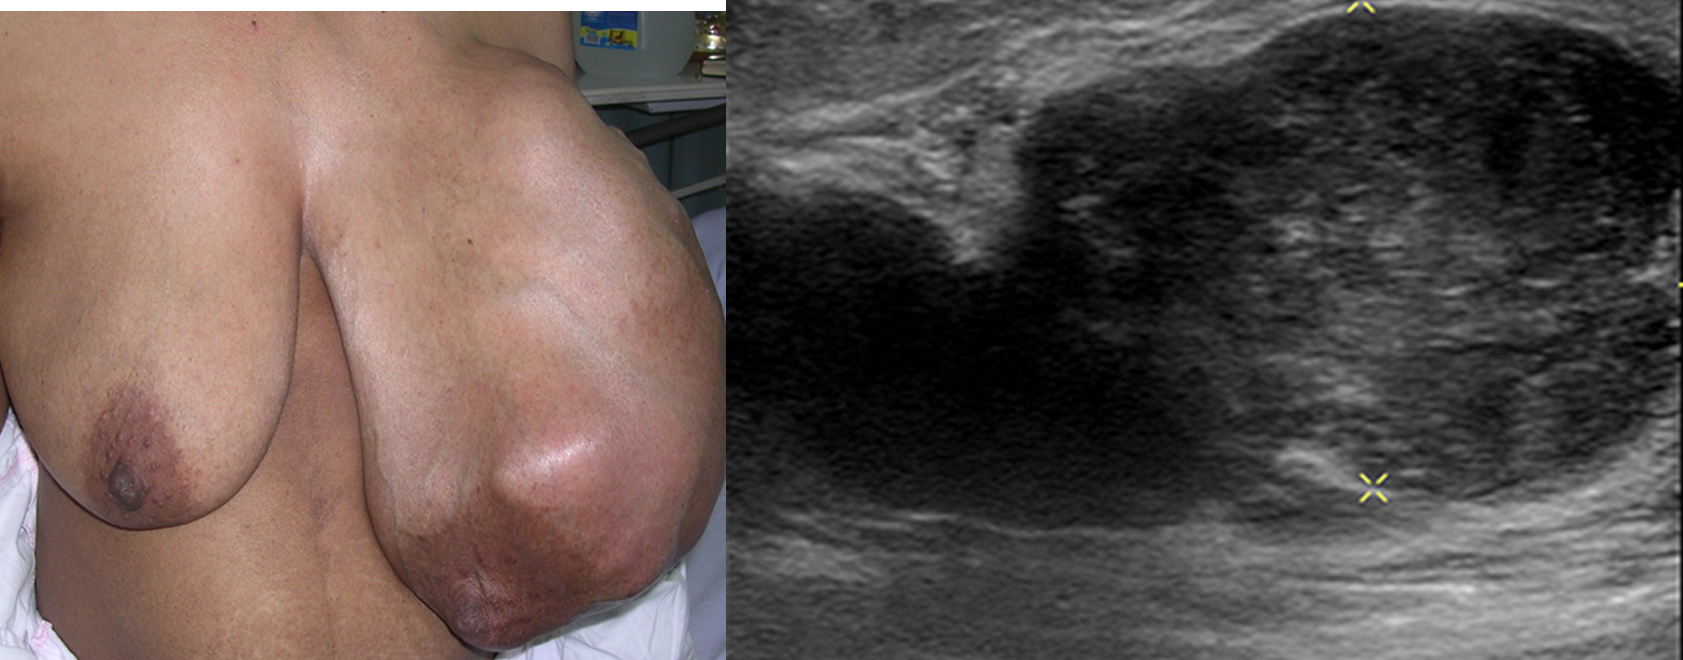

Fibroepithelial tumor

• Usually large, bosselated, no attachment.

• Mastectomy for very large lesions.